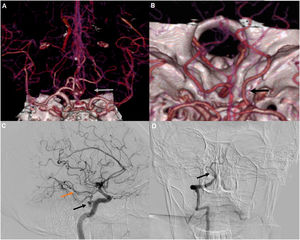

In this cohort, the anatomical variants were associated with the development of DCI and poor neurological outcome. The distribution of anatomical variations in this cohort, was as follows: 1 patient (1.21%) had a persistent trigeminal artery (PTA), 6 patients (7.3%) had either agenesis or hypoplasia of the A1 segment of anterior cerebral artery, 9 patients (10.9%) had either a complete or partial fetal posterior cerebral artery, and 3 patients had a hypoplastic vertebral artery (3.7%) (Fig. 2). Table 4 shows the patients affected by DCI, with anatomical variants, the respective arterial territory involved, and mRS at discharge.

Anatomic variations in our sample, 3D-CTA (A) and (B) A. Absence of an A1 segment of the right anterior cerebral artery (white arrow). B. Right posterior fetal cerebral artery (black arrow). The P1 segment is absent. DSA image of the right internal carotid and right vertebral artery (C) and (D). C. Trigeminal persistent artery arising from the cavernous segment of the internal carotid (Black arrow), posterior communicating artery, (orange arrow). D. Hypoplasia of the basilar artery (black arrow).

What allowed us to confirm that it were indeed anatomical variants and not vasospasm secondary to SAH, were the imaging and TCD indirect findings, particularly bony structures, vessel's diameters, and Soustiel index (“modified Lindegaard” index) (for basilar artery). In case of hypoplastic vertebral arteries (HVA) (2 cases), we compared the size transverse foramen of C6 and C2 with the contralateral one, and also estimated the diameter difference of the artery (which was 2.05 mm). Regarding the only case of hypoplastic basilar artery (HBA), we measured the artery's diameter (1.92 mm), and we obtained a normal Soustiel index by TCD means, confirming that it corresponds to anatomical variants.

Although many cerebral arterial variants may be asymptomatic, their recognition is important, as some of these might be pathological and play an important role in the planning of neurosurgical procedures.15 The anatomy of the brain arterial system can influence the development of vascular diseases like aneurysms, dolichoectasia, atherosclerosis, stroke, and, as we propose in this paper, DCI.29 Developmental variants of the cerebral circulation can be fenestrations and duplications, variants of the circle of Willis, persistent carotid-basilar anastomoses, and other vascular anomalies identified in the skull base.30 The most frequently reported persistent variant fetal arteries in adults include the persistent trigeminal artery (PTA) (0.1%–0.5%), hypoglossal artery (0.1%), proatlantal artery (0.020%), and otic artery (0.001%).31 There are some few but important caveats that are worth-mentioning regarding some of these vessels and how they are related to cerebrovascular disease. Fetal posterior cerebral artery (FPCA), PTA, and hypoglossal arteries increased the likelihood of aneurysm formation in-situ or distant and rupture due to turbulent flow and increased wall shear stress.29 They have also been associated with ischemic cerebrovascular disease (either transient ischemic attack or ischemic stroke), and also with the presence of other important vascular arterial malformations (FPCA, A1 segment hypoplasia, or azygos anterior cerebral artery).30,32–35 PTA arises from the cavernous ICA in the region where it leaves the carotid canal and joins the basilar artery through the sella turcica, normally regressing.36 Both PTA and fetal posterior cerebral artery supply the posterior cerebral territory via the anterior cerebral circulation.37